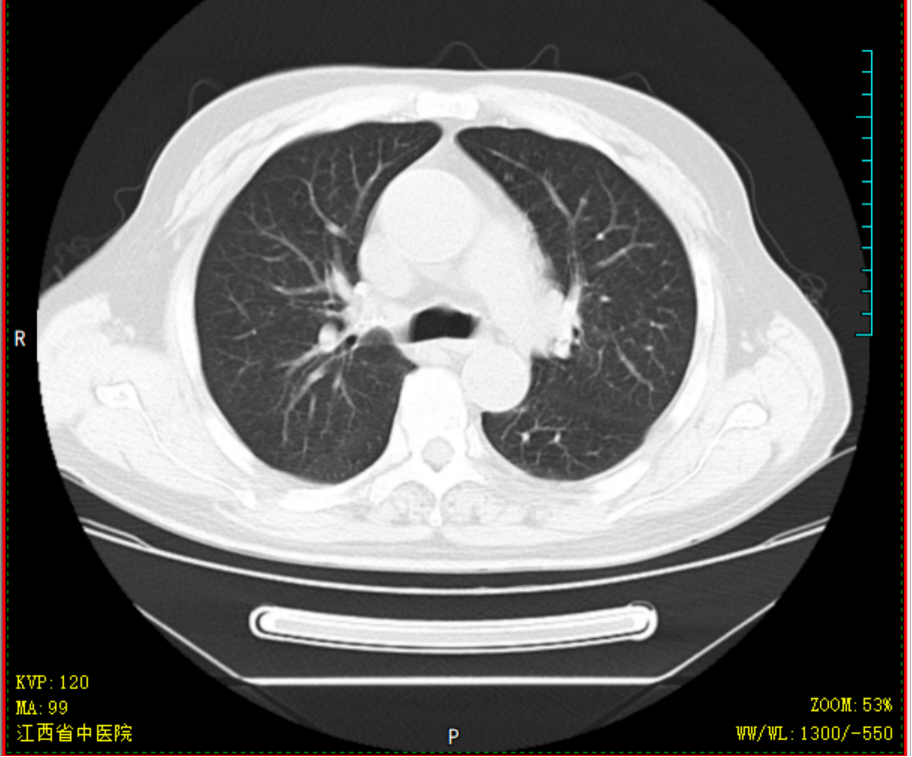

胡大爷,男,69岁,2020-4-14因“头晕乏力”就诊某省级医院,完善骨髓细胞学等检查后诊断为AML-M2a型,中危组;排出化疗禁忌症后,予标准DA方案化疗治疗,化疗过程中出现持续高热,热峰39.5℃,肺部感染、重症肺炎,恶心呕吐明显,予美罗培南+万古霉素抗感染,伏立康唑抗真菌感染,输注红细胞、血小板等治疗,化疗结束后复查骨髓细胞学示AML-NR骨髓象(急性髓系白血病未缓解骨髓象),经40天住院治疗病情平稳后出院,出院时体重减轻10kg。因为恐惧化学治疗,自行停化疗。2020-07-23患者因疲劳乏力加重就诊于金瓶梅电影 ,要求中医调理,入院查血常规示重度贫血、血小板减少,生化示肝功能不全、高尿酸;骨髓提示AML-NR骨髓象(急性髓系白血病未缓解骨髓象)。入院后予中药汤剂益气养血,并热敏灸温通经络。经治疗后患者乏力疲劳、贫血明显改善,排除治疗禁忌后,08-13起减低剂量化学治疗,同时口服我科经验方参芪杀白汤益气养血、扶正祛邪抗肿瘤,同时调理脏腑气机减少化疗不良反应,起增效减毒之功;热敏灸疗法灸肺腧穴固护肺卫之气预防外邪入侵,灸脾腧穴、肾腧穴固先后天之本促进气血化生。全程未出现呕心呕吐、骨髓抑制等常见不良反应,09-07骨髓细胞学示AML-CR骨髓象(急性髓系白血病完全缓解骨髓象)、白血病微小残留MRD提示阴性。2020-09-08返院行中西医结合方案抗白血病治疗,过程顺利,结束治疗后09-15出院 。经西医结合治疗不但是患者的症状改善明显,同时提高患者生活质量,同时保证了患者的临床疗效。